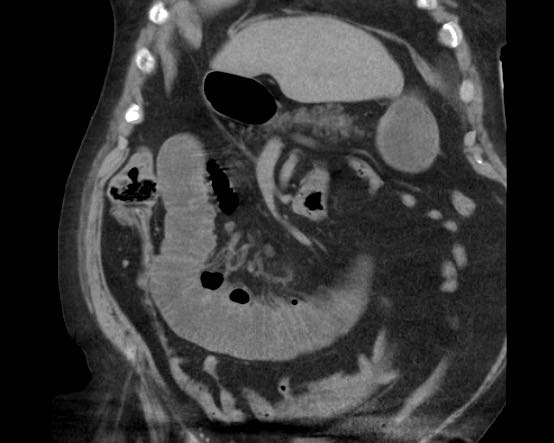

CT trong viêm túi mật cấp

CT có thể rất hữu ích trong các trường hợp siêu âm không cho kết quả chẩn đoán.

Đây là hình ảnh của một bệnh nhân béo phì với đau hạ sườn phải cấp tính trong 6 giờ. CRP 2.

Siêu âm cho thấy túi mật lớn có bùn mật, không quan sát thấy sỏi.

Việc ấn vào túi mật không đáng tin cậy do vị trí cao dưới cung sườn phải.

Không có bất thường siêu âm nào khác.

CT thực hiện cùng ngày cho thấy túi mật lớn với chỉ những thay đổi quanh túi mật kín đáo và không có nguyên nhân nào khác giải thích cho các triệu chứng.

Ngày hôm sau CRP là 105 và CT không tiêm thuốc cản quang lặp lại cho thấy quầng mờ xung quanh túi mật.

Phẫu thuật tiếp theo xác nhận viêm túi mật cấp giai đoạn sớm do sỏi nhỏ trong ống túi mật.